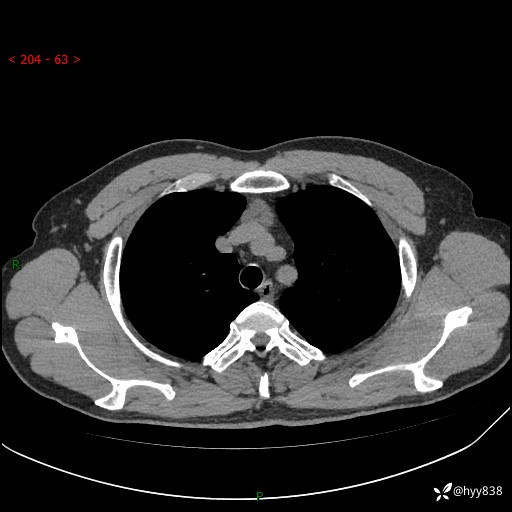

患者性别:女

患者年龄:49岁

简要病史:跟骨骨折,常规CT发现纵隔占位

胸部CT平扫